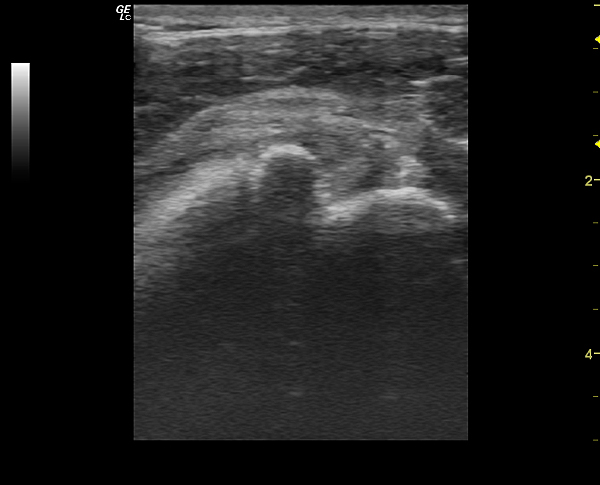

На представленных сонограммах сканирована головка плечевой кости с ротаторной манжетой.